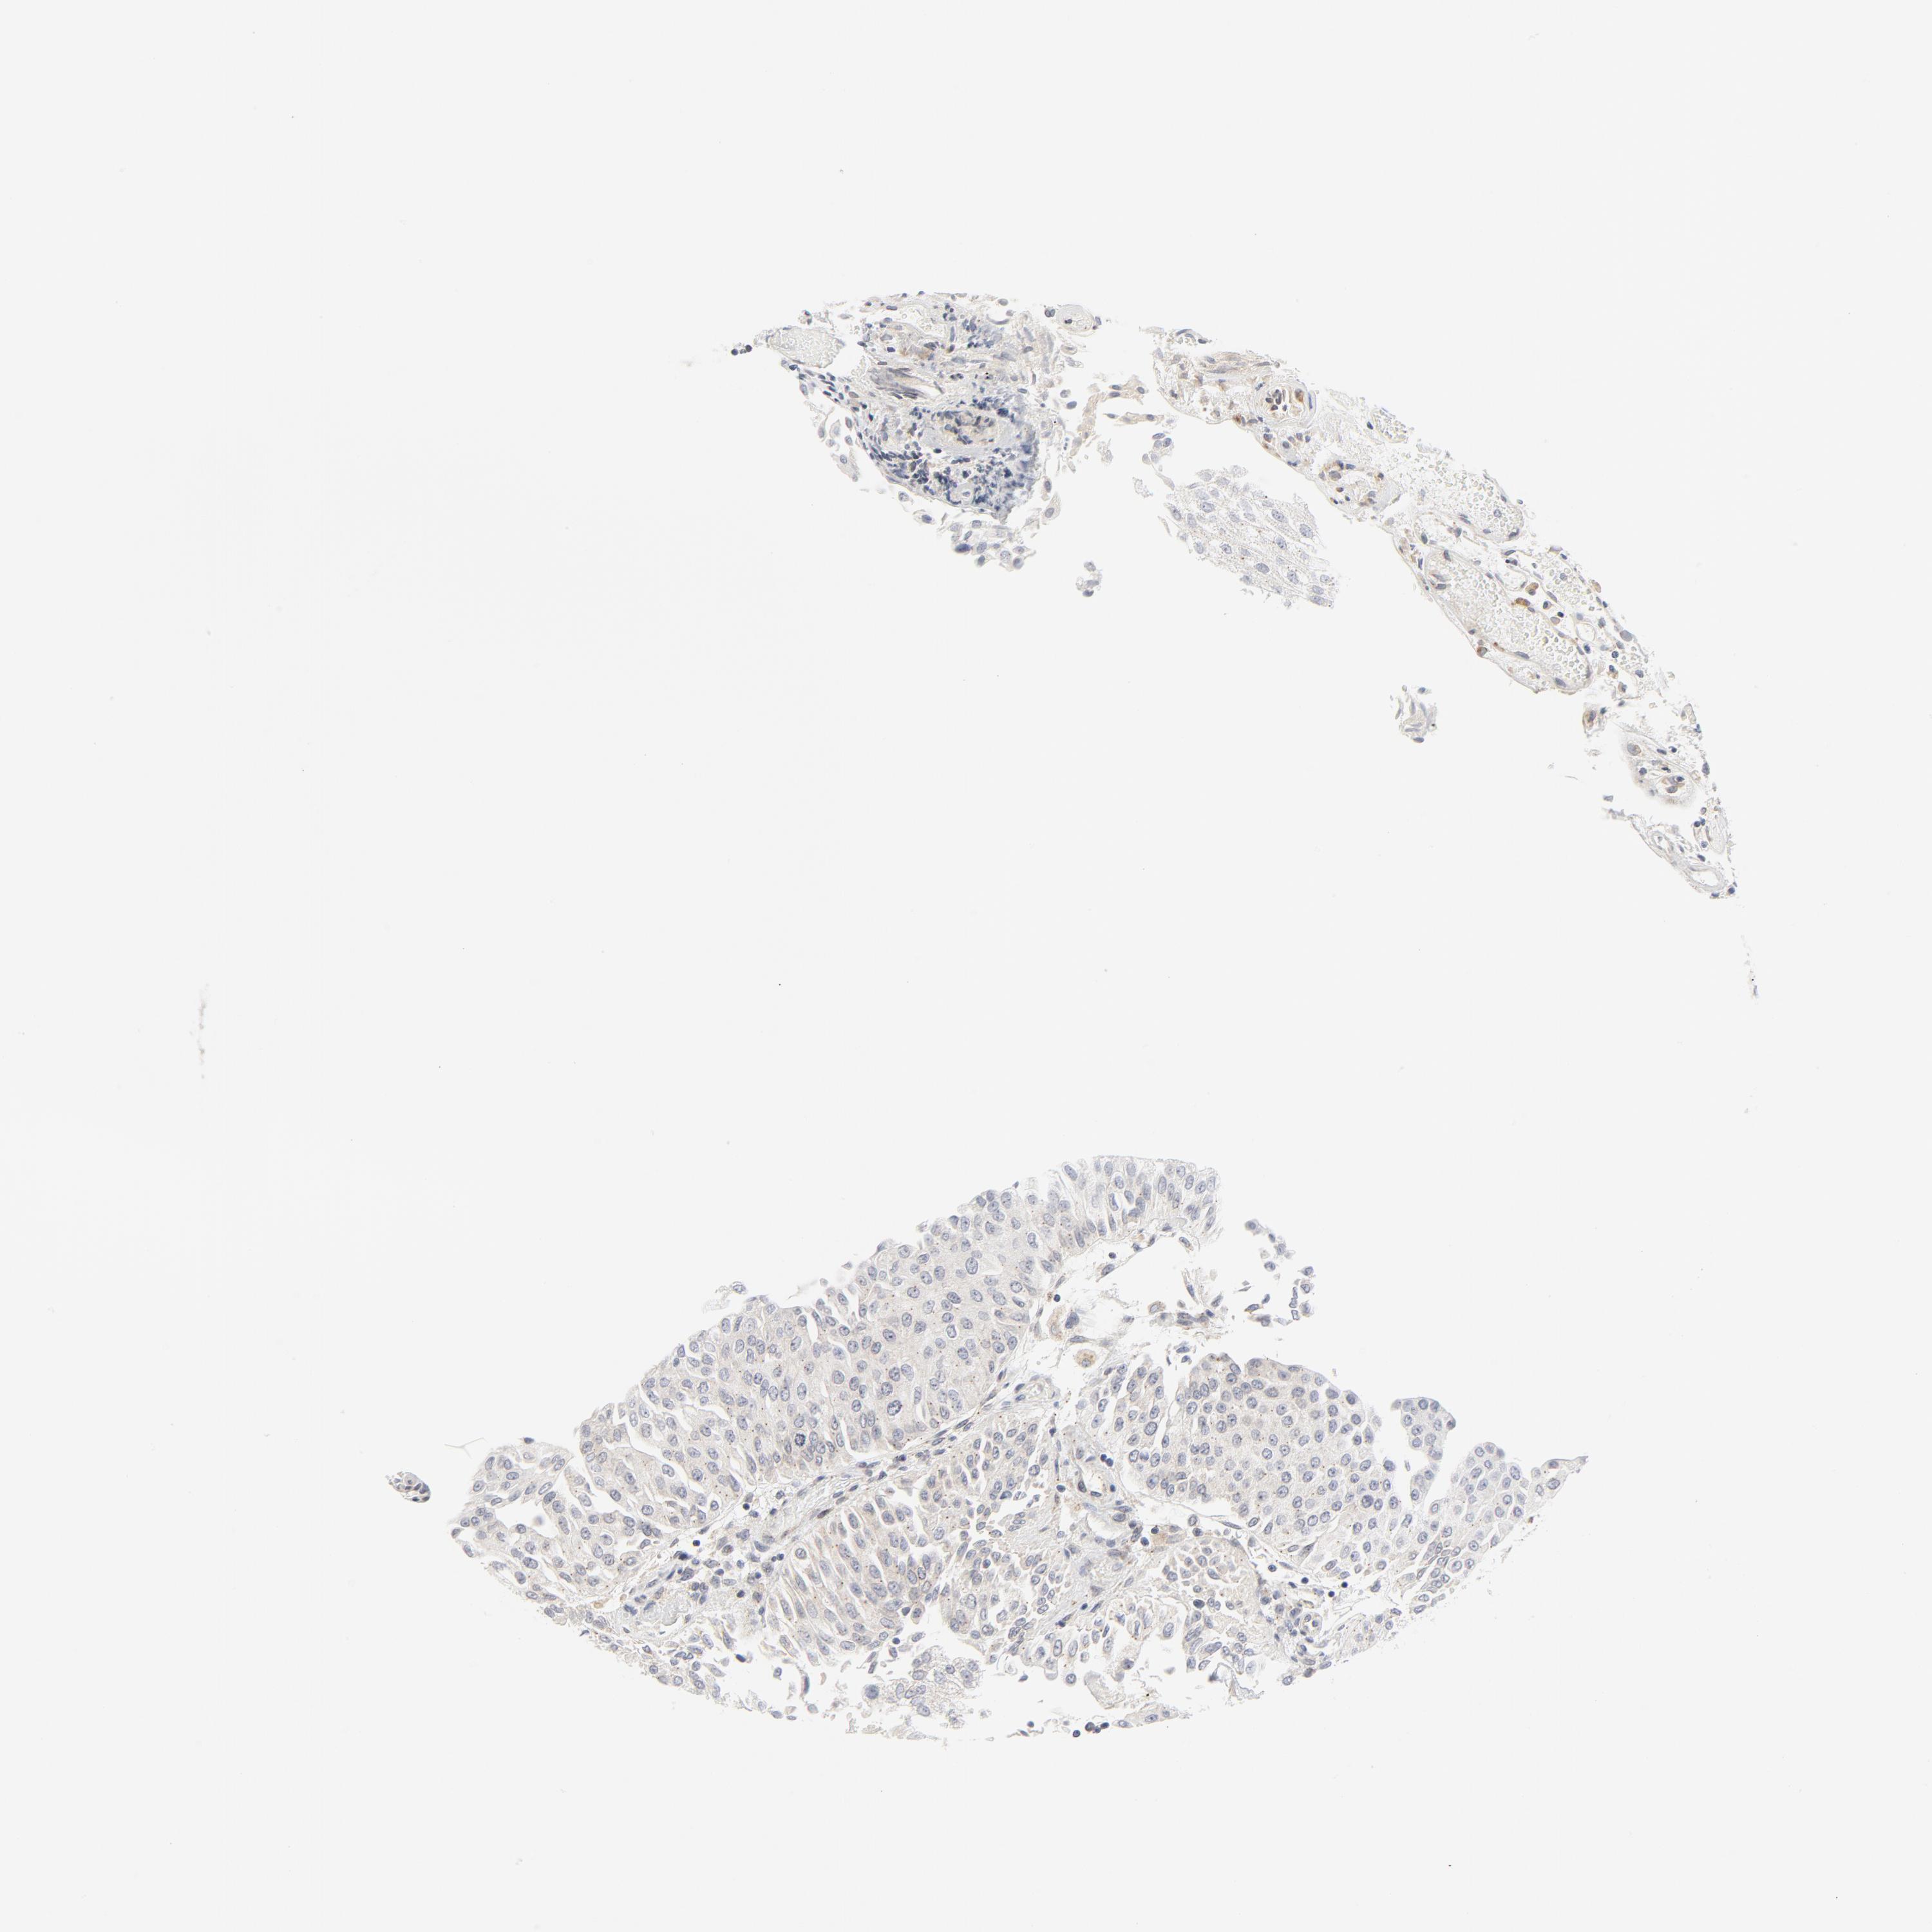

UROTHELIAL CANCER - Protein expressioni

A mouse-over function shows sample information and annotation data. Click on an image to view it in a full screen mode. Samples can be filtered based on level of antibody staining by selecting one or several of the following categories: high, medium, low and not detected. The assay and annotation is described here.

Note that samples used for immunohistochemistry by the Human Protein Atlas do not correspond to samples in the TCGA dataset.

Antibody stainingi

Antibody staining in the annotated cell types in the current human tissue is reported as not detected, low, medium, or high, based on conventional immunohistochemistry profiling in selected tissues. This score is based on the combination of the staining intensity and fraction of stained cells.

Each image is clickable and will lead to virtual microscopy that enables deeper exploration of all samples and also displays staining intensity scores, fraction scores and subcellular localization as well as patient and tissue information for each sample.

Antibody HPA029925

Antibody CAB004490

Urothelial carcinoma, Low grade

Urothelial carcinoma, High grade